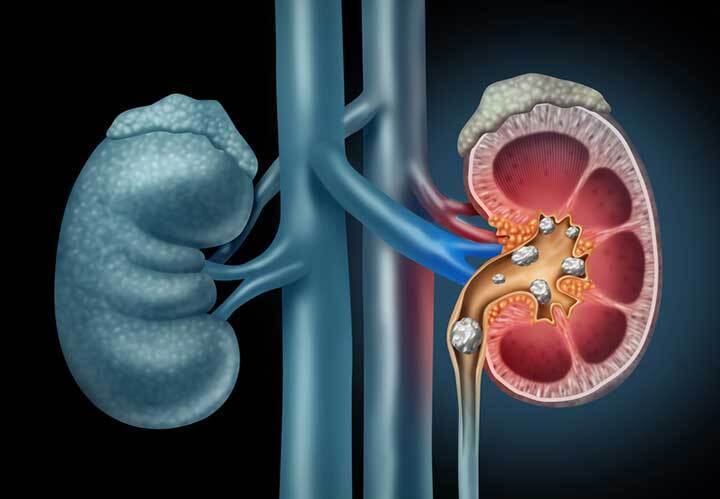

801克!斯里兰卡一老兵体内取出吉尼斯认证的世界最大肾结石

2023年6月14日周三,斯里兰卡军方官宣,该国军医已经从一名62岁的退役士兵体内切除了目前被吉尼斯世界纪录认证的世界上最大的肾结石。

消息称 ,从前中士卡尼斯图·孔吉体内取出的巨大肾结石最大长度达13.37厘米,比普通人肾脏轴向10至12厘米的长度还要长;结石重达801克,则是普通男性肾脏重量的5倍以上。

吉尼斯世界纪录官网已经对这一创世界纪录的巨大肾结石进行了认证:结石最大长径13.372厘米,

于2023年6月1日在斯里兰卡科伦坡的Canistus Coonghe被取出。

此前该项纪录为13厘米,重量为620克。